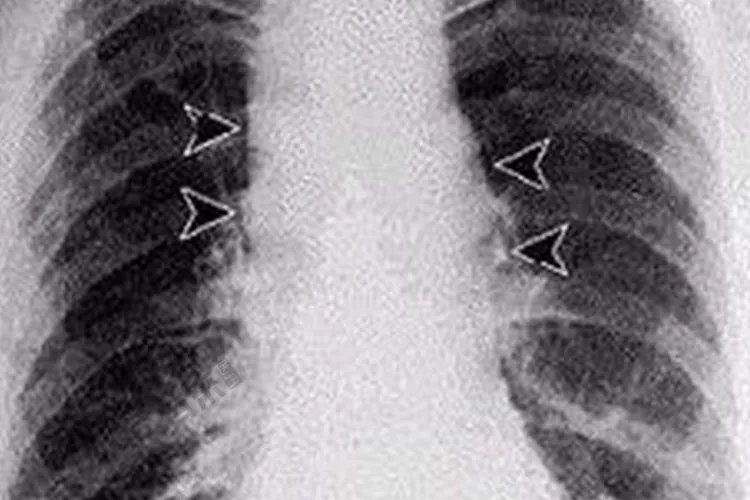

病因人类炭疽的主要传染源是患病的动物,它们的皮毛、肉、骨粉等均可携带细菌造成传播。炭疽患者的痰、粪便及病灶分泌物可检出细菌具有传染性,但人与人之间的传播极少见。肺炭疽多为原发性,主要通过呼吸道吸入带有炭疽杆菌芽胞的粉尘或气溶胶引起,也可继发于皮肤炭疽。诊断本病可根据患者的病史,如是否生活在存在炭疽的地区,是否从事与畜产品密切接触的职业是否食用过可疑肉制品等,结合患者的临床症状及实验室检查及影像学检查进行疾病的诊断。X线胸片可见纵隔增宽肺部炎症水肿、栓塞和胸腔积液等征象。治疗一般治疗严格隔离患者,对其分泌物、排泄物按芽孢消毒方法进行处理,需对症治疗。不能进食者可予以输液,出血严重者适量输血,有循环衰竭者,进行抗休克治疗。病原治疗青霉素为最有效的抗生素,应及时足量应用。抗血清治疗对重症者可用,应用前必须先作皮试。